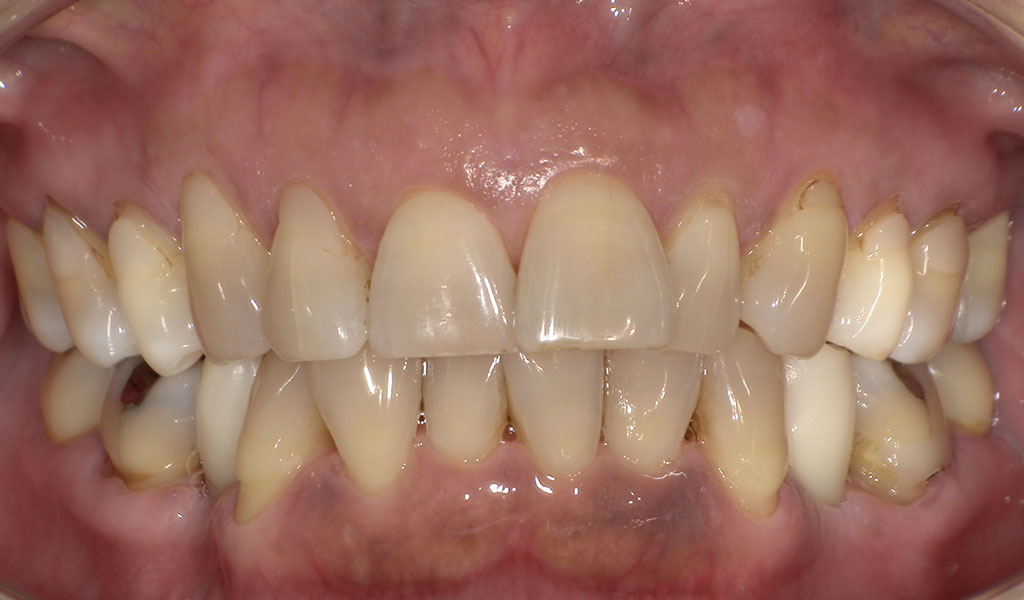

After3

After4